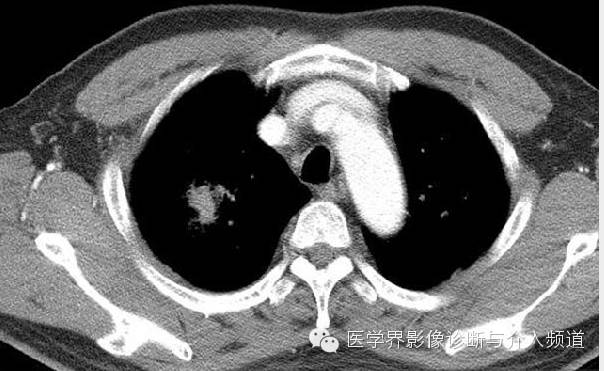

男,59岁,主诉咳嗽和痰中带血

CT显示右肺上叶实性团块病灶内不规则空洞形成,周围可见GGO,右侧胸腔少量积液。患者外周血嗜酸性粒细胞增多和Pw抗体阳性。治疗后X线平片显示右上肺结节影缩小。治疗前X线片显示病灶位于右肺上野,右侧肋膈角变钝。此外,X线平片示主支气管节段性偏心性狭窄,这是由于胸内甲状腺肿外在压迫所造成。

肺血吸虫病